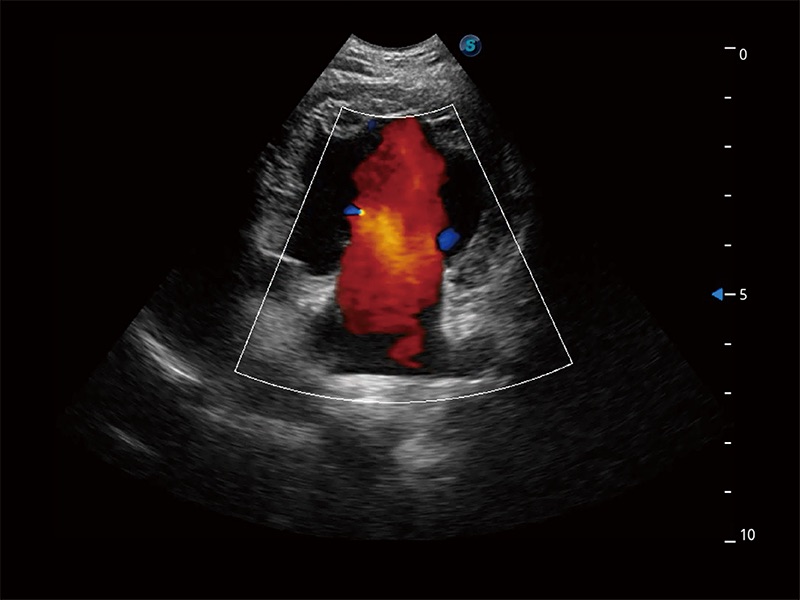

高性能和先进的临床应用工具可以为动物医生提供临床信心。ProPet 80 搭载了先进的腹部和浅表应用工具,帮助医生在日常临床实践中发挥前所未有的作用。

极大提升超低速微细血流的检出能力,同时更精准地滤除软组织和超声信号,为兽用医生提供以往无法通过常规血流获得的疾病诊断信息。

在传统二维血流成像的基础上,呈现血流的立体感,具有动感的生命力之美。即便是微小的血管也能轻松应对,提高了血流的视觉敏感性。